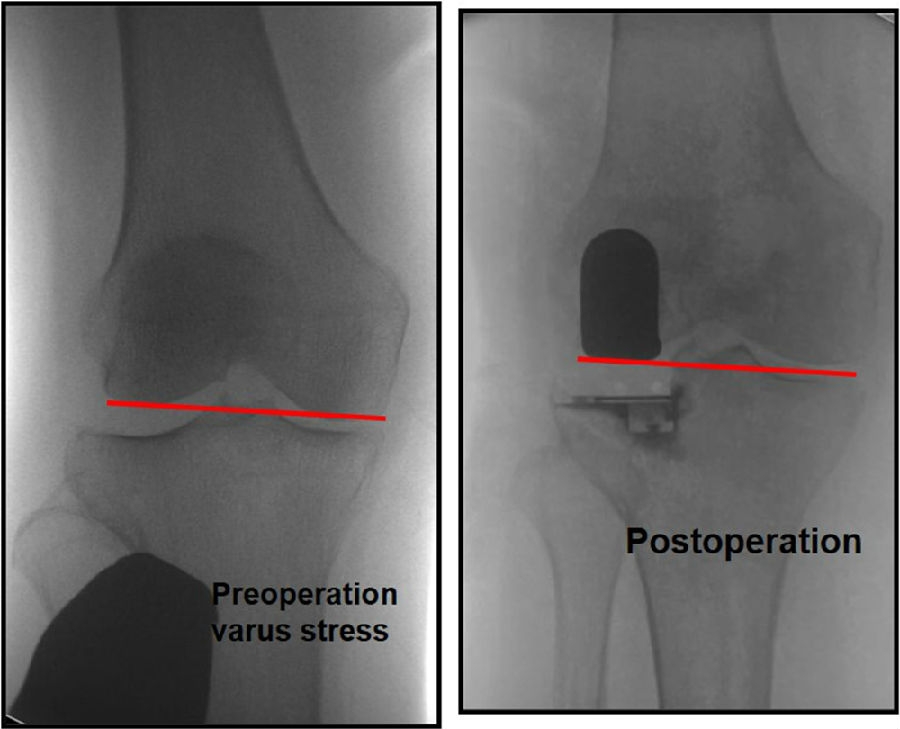

外侧OA多发生在股骨侧,常伴有外侧股骨髁发育不良。通常需要做内翻应力位判断外侧间隙张开程度及胫骨磨损程度。

胫骨截骨应尽可能保守,通常2-3mm即可,以利用胫骨近端皮质的强度,并可增大承载面积。

关键技术2:恢复关节线

重建关节线意义重大,因为关节线的抬高可能导致不稳定。

可能引起抬高关节线的操作:通过过度研磨股骨远端,试图匹配屈伸间隙;通过在屈曲位选择垫块厚度导致外侧间室过度填塞。

外侧间室在自然屈曲状态下松弛,将允许更厚的胫骨垫片插入,所以LUKA应在伸直位选择垫片厚度,从而达到“平衡”。